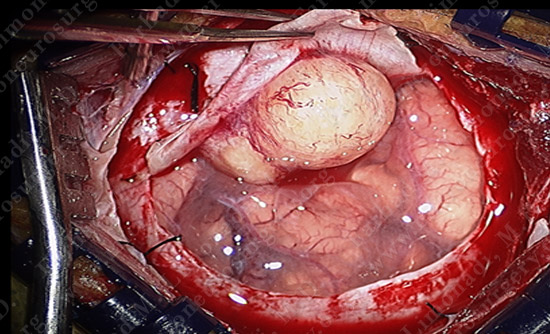

Surgical Protection

- Small circular bone flap is elevated using computer localization. The dura overlying the tumor excised and the tumor revealed.